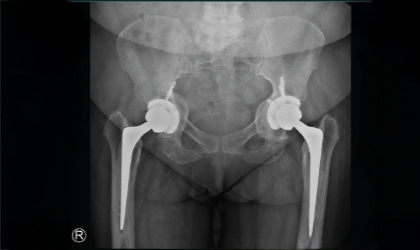

Bilateral Hip Recovery

This 34 year old medical representative had avascular necrosis with collapse of both her hips